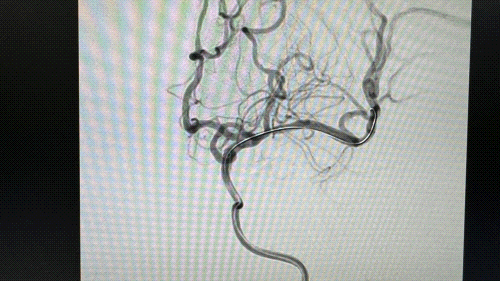

因患者已行头颈部血管CTA检查,成像质量满意,造影就直接使用弓内造影并观察头颈部血管情况。

直接造影显示左侧大脑中动脉闭塞。